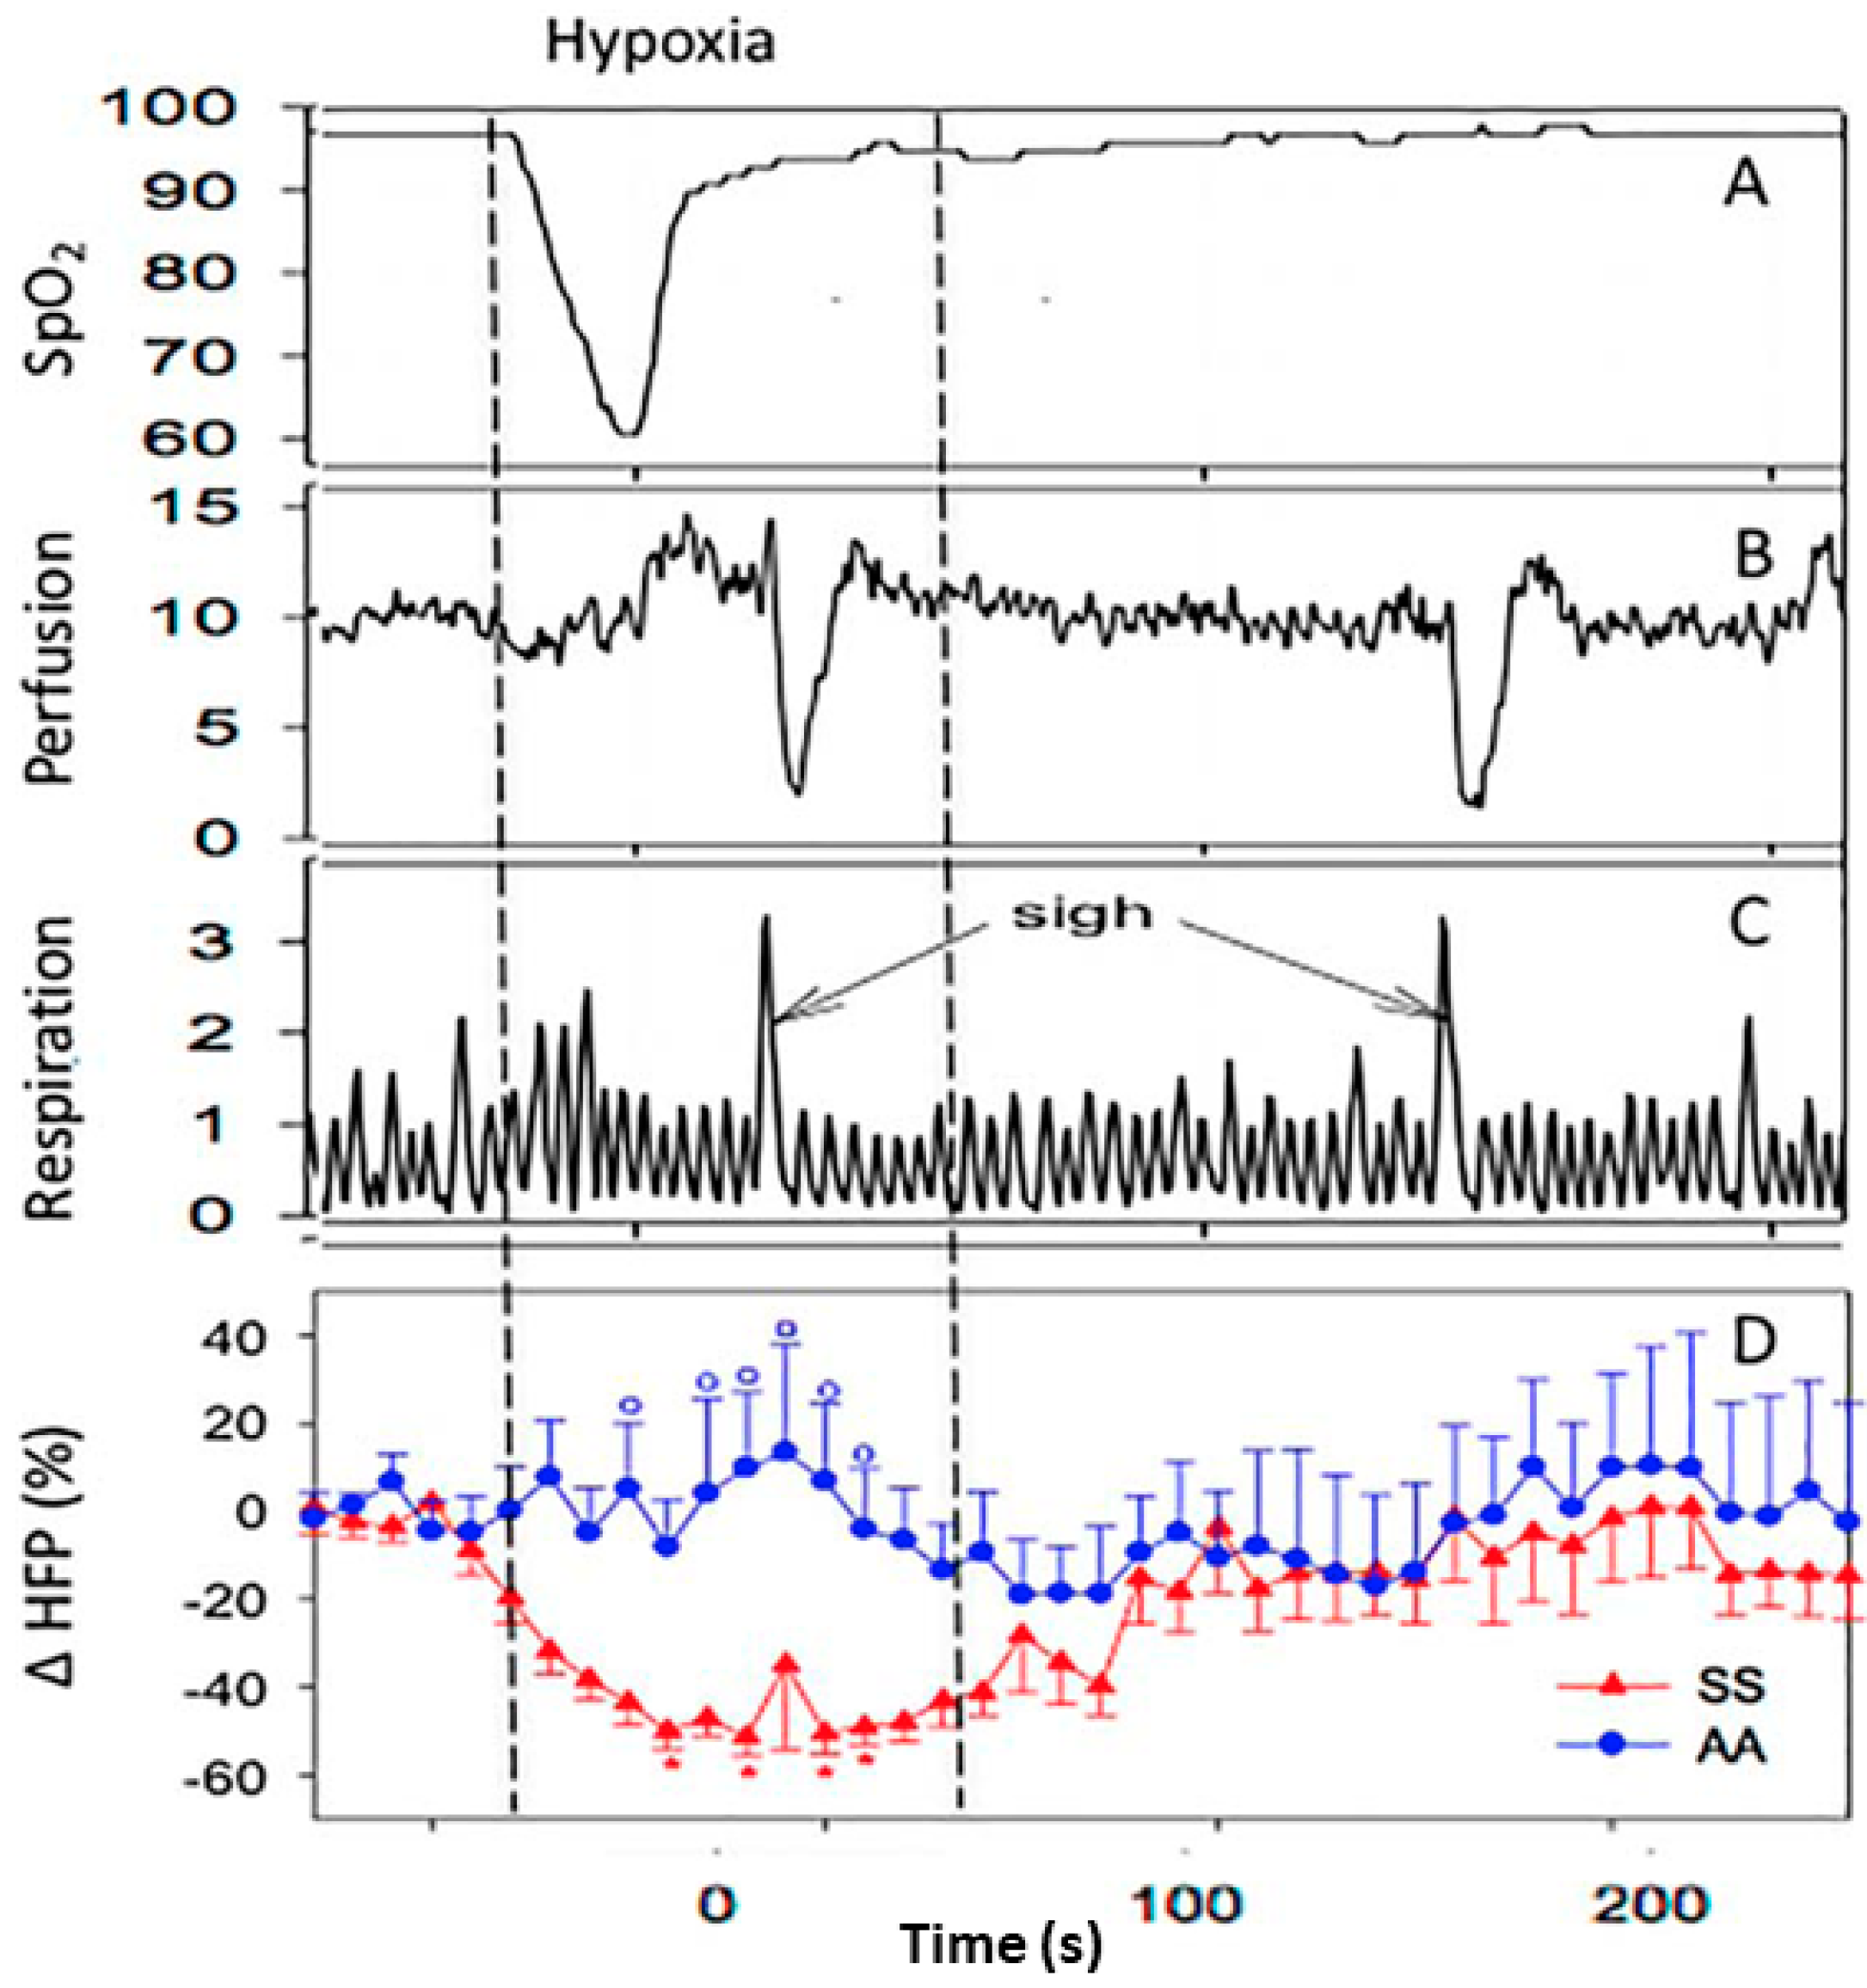

Early Detection of Vascular Disorders

High-Accuracy, Low-Fidelity Acoustic Sensing for Vaso-Occlusion Detection

Our latest project integrates advanced signal processing with machine learning algorithms to extract high-quality diagnostic information from low-fidelity acoustic data, potentially revolutionizing early detection of vascular disorders.